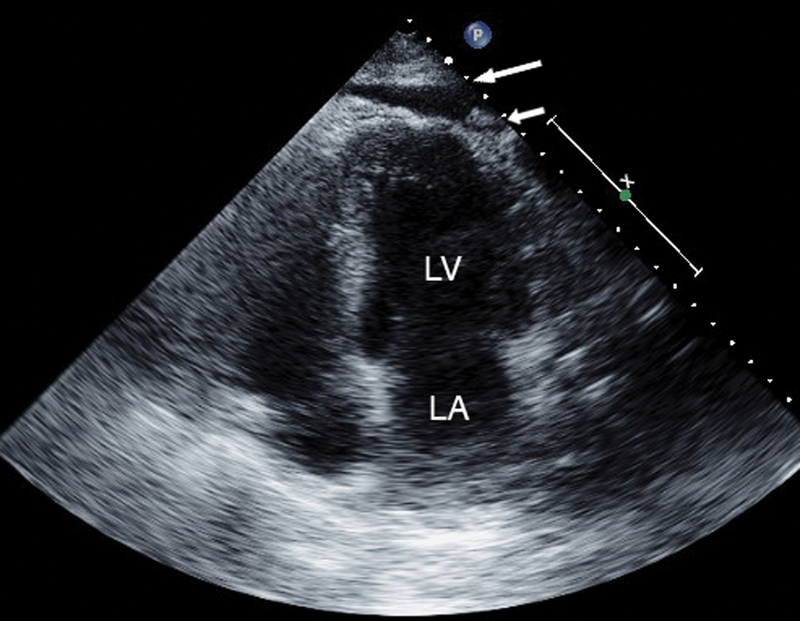

فحوصات تشخيصية لبعض امراض القلب والشرايين التاجية